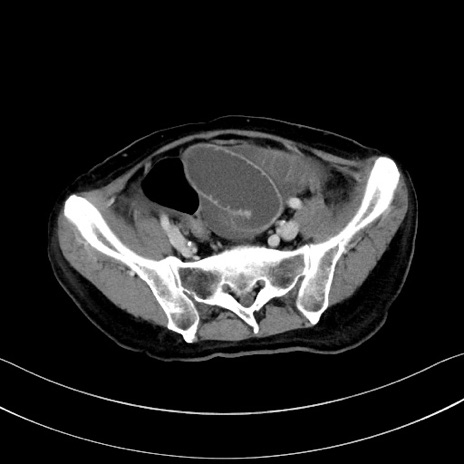

冠状断像

【症例】60歳代男性

【主訴】嘔吐

【現病歴】胃癌にて胃全摘後。食思不振が悪化し、夜中に嘔吐することがある。

【既往歴】胃癌、胃全摘、脾摘、胆摘後

【データ】WBC 5900、CRP 10.56